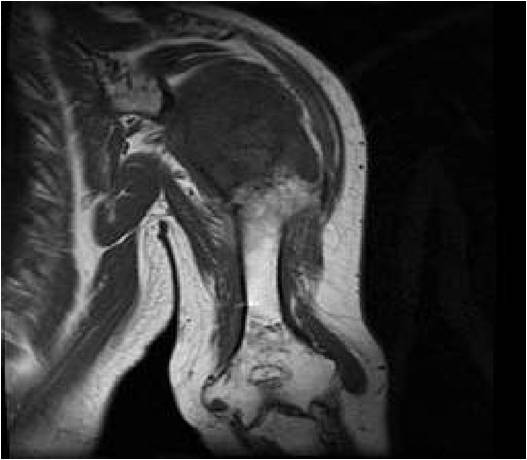

MRI:

- T1 Weighted Images: Intermediate Signal Intensity

- Calcifications will be low signal

T1: Intermediate Signal Lobular Growth